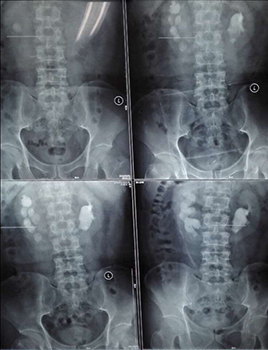

兩位患者均因腰背部疼痛來我院看診,住院后行CT等檢查確診為馬蹄腎合并腎結(jié)石,一例左腎結(jié)石大小約2.5cm,另一例右腎結(jié)石大小約3.0cm。

經(jīng)皮腎鏡取石術(shù)是泌尿外科風(fēng)險(xiǎn)最大、技術(shù)要求最高的手術(shù)之一,而馬蹄腎是一種先天性畸形,本該相對獨(dú)立的左右兩腎的上端或者下端長在一起,形似“U”形馬蹄,且腎旋轉(zhuǎn)不良,腎盞位于腎前方,輸尿管走形異常,所以馬蹄腎患者更易出現(xiàn)各種合并癥,例如泌尿系統(tǒng)結(jié)石、感染、腎積水、尿路梗阻等。這種腎畸形增加了經(jīng)皮腎鏡取石手術(shù)的定位穿刺和建立操作通道的難度,術(shù)中出血風(fēng)險(xiǎn)也更高。如果通道建立不理想,可能找不到結(jié)石,無法完成碎石取石。

馬蹄腎